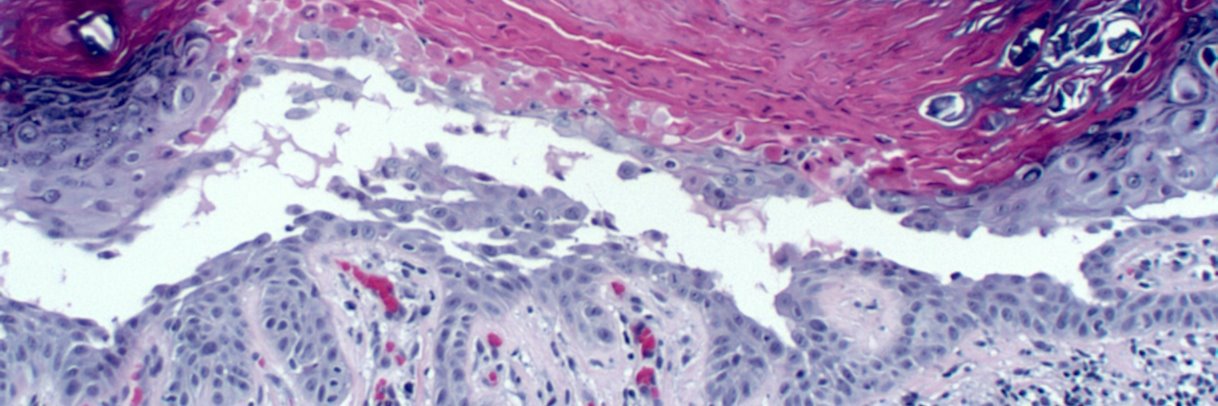

🔬Molluscum contagiosum.

👤72F. Chest.

Textbooks say it is a childhood disease or passed sexually. Anecdotally, any body can get it anywhere at any age.

#dermpath #dermatology #dermtwitter #pathology